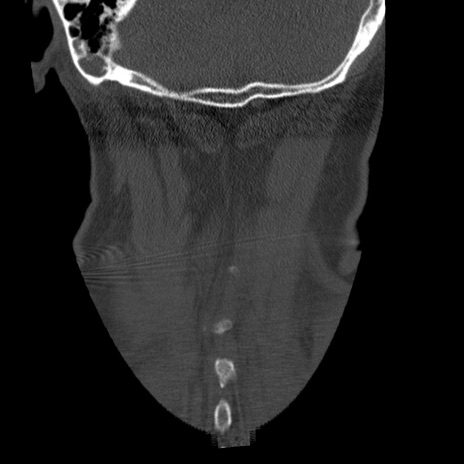

症例50 頚椎CT(冠状断像)

頚椎CT